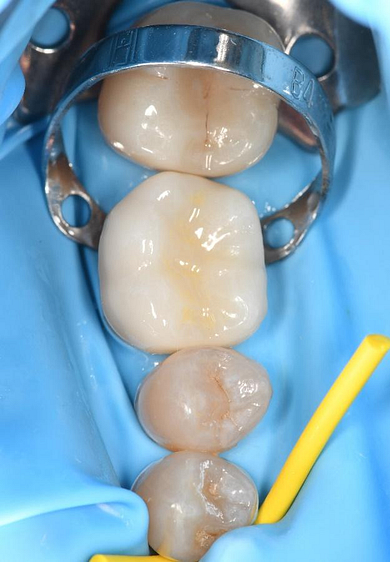

The crown was milled from a high-strength, multilayered zirconia and hand-finished to achieve a lifelike appearance.

At the final appointment, the crown was securely attached to the implant, resulting in a beautiful, natural-looking restoration.

The implant-supported crown seamlessly integrated with the patient's natural dentition, and the patient reported excellent comfort and function.